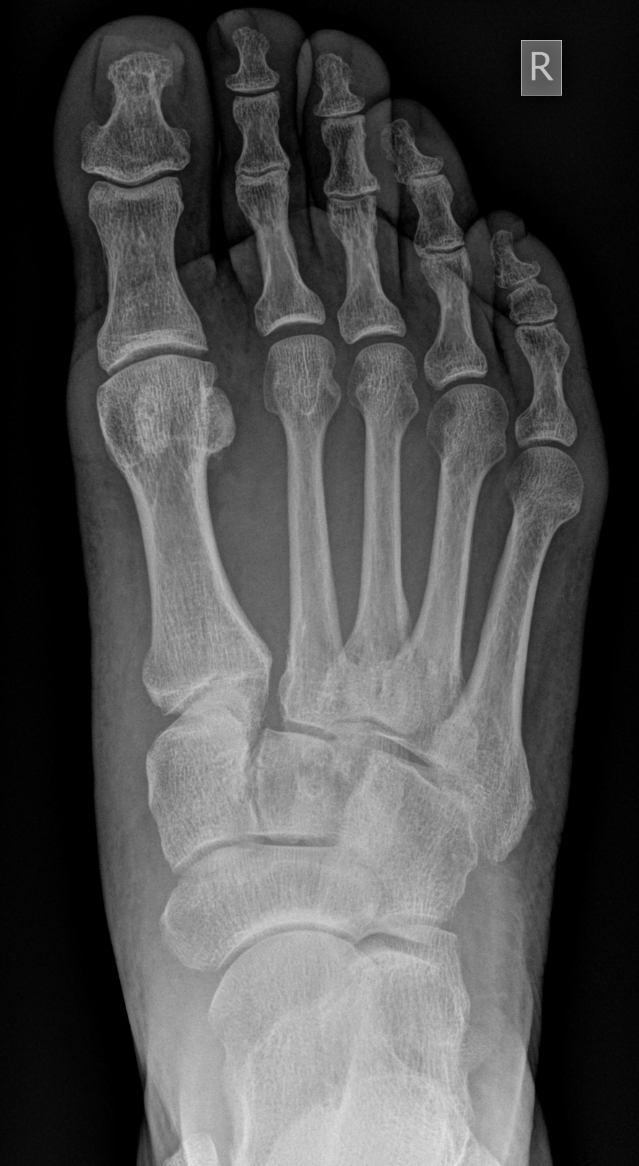

3. Lis Franc Injury